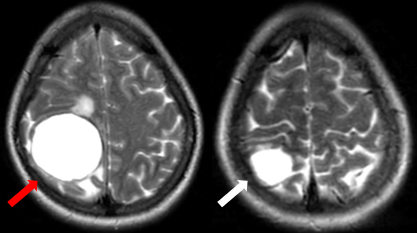

Sau 8 tháng điều trị, bệnh nhân không còn ghi nhận những cơn co giật, bệnh nhân không khó thở, không đau ngực. Trên phim chụp cộng hưởng từ não, kích thước khối u giảm đáng kể là một minh chứng cho sự đáp ứng tốt với thuốc của bệnh nhân. Phim chụp cắt lớp vi tính cũng ghi nhận kích thước khối u giảm hơn so với phim chụp cũ.

Hình 3. Hình ảnh phim chụp cộng hưởng từ não ngày 28 tháng 6 năm 2023 (mũi tên trắng) so với ngày 27 tháng 10 năm 2022 (mũi tên đỏ), kích thước khối u giảm so với phim chụp cũ.